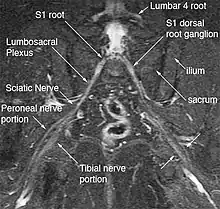

The most significant impact of magnetic resonance neurography is on the evaluation of the large proximal nerve elements such as the brachial plexus (the nerves between the cervical spine and the underarm that innervate shoulder, arm and hand),[9] the lumbosacral plexus (nerves between the lumbosacral spine and legs), the sciatic nerve in the pelvis,[10] as well as other nerves such as the pudendal nerve[11] that follow deep or complex courses.

Neurography has also been helpful for improving image diagnosis in spine disorders. It can help identify which spinal nerve is actually irritated as a supplement to routine spinal MRI. Standard spinal MRI only demonstrates the anatomy and numerous disk bulges, bone spurs or stenoses that may or may not actually cause nerve impingement symptoms.[12][13]

Many nerves, such as the median and ulnar nerve in the arm or the tibial nerve in the tarsal tunnel, are just below the skin surface and can be tested for pathology with electromyography, but this technique has always been difficult to apply for deep proximal nerves. Magnetic resonance neurography has greatly expanded the efficacy of nerve diagnosis by allowing uniform evaluation of virtually any nerve in the body.[14][15][16][17]